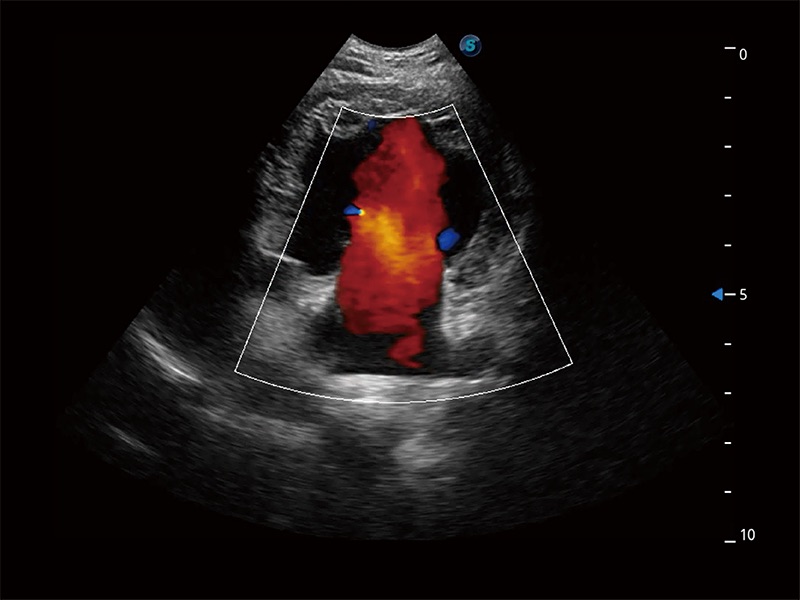

非線性融合造影成像充分利用諧波和基波信號,為難以觀察的血流進(jìn)行增強(qiáng)顯像??捎糜诰€陣、凸陣、微凸陣、相控陣探頭。

ProPet 80 配備了豐富的心臟探頭群、先進(jìn)的成像技術(shù)和專業(yè)的心臟測量工具,可幫助動物醫(yī)生為不同體型和生理結(jié)構(gòu)的動物提供心臟和心肌功能的全面評估。